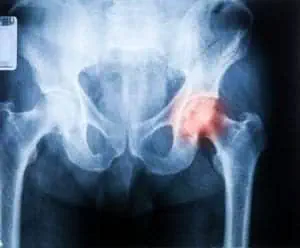

Artros definieras som en nedbrytande (=degenerativ) förändring i leden och vid MR går det att observera slitage. Det är en degenerativ sjukdom som gör att ledbrosken bryts ned snabbare än den återbyggs. När brosken minskar eller försvinner uppstår smärta och i varierande grad rörelsehinder. Artros är vanligt i knä och höft.En vanlig symptombild är långsamt ökande värk och stelhet i leden, ofta på morgonen och efter aktivitet. Besväret lindras när ”man kommit igång och blivit varm”. Efter lång- varig problematik kan smärta uppstå även i aktivitet och i vila. Fram till för några år sedan var det en negativ utveckling för artrospatienter där vila eller operation var de enda utvägarna. Nyare forskning visar att belastning, mer specifikt tung styrketräning, har en positiv effekt och kan reversera de strukturella förändringarna.

Artrosen ger till en början smärta vid aktivitet, och ju längre gången sjukdomen är ju mer inträder vilovärk. Är du över 40 år och har värk i höften som även känns mot låret eller knät, kan det vara vettigt att misstänka artros. Detta bekräftas eller avfärdas med en röntgenbild.